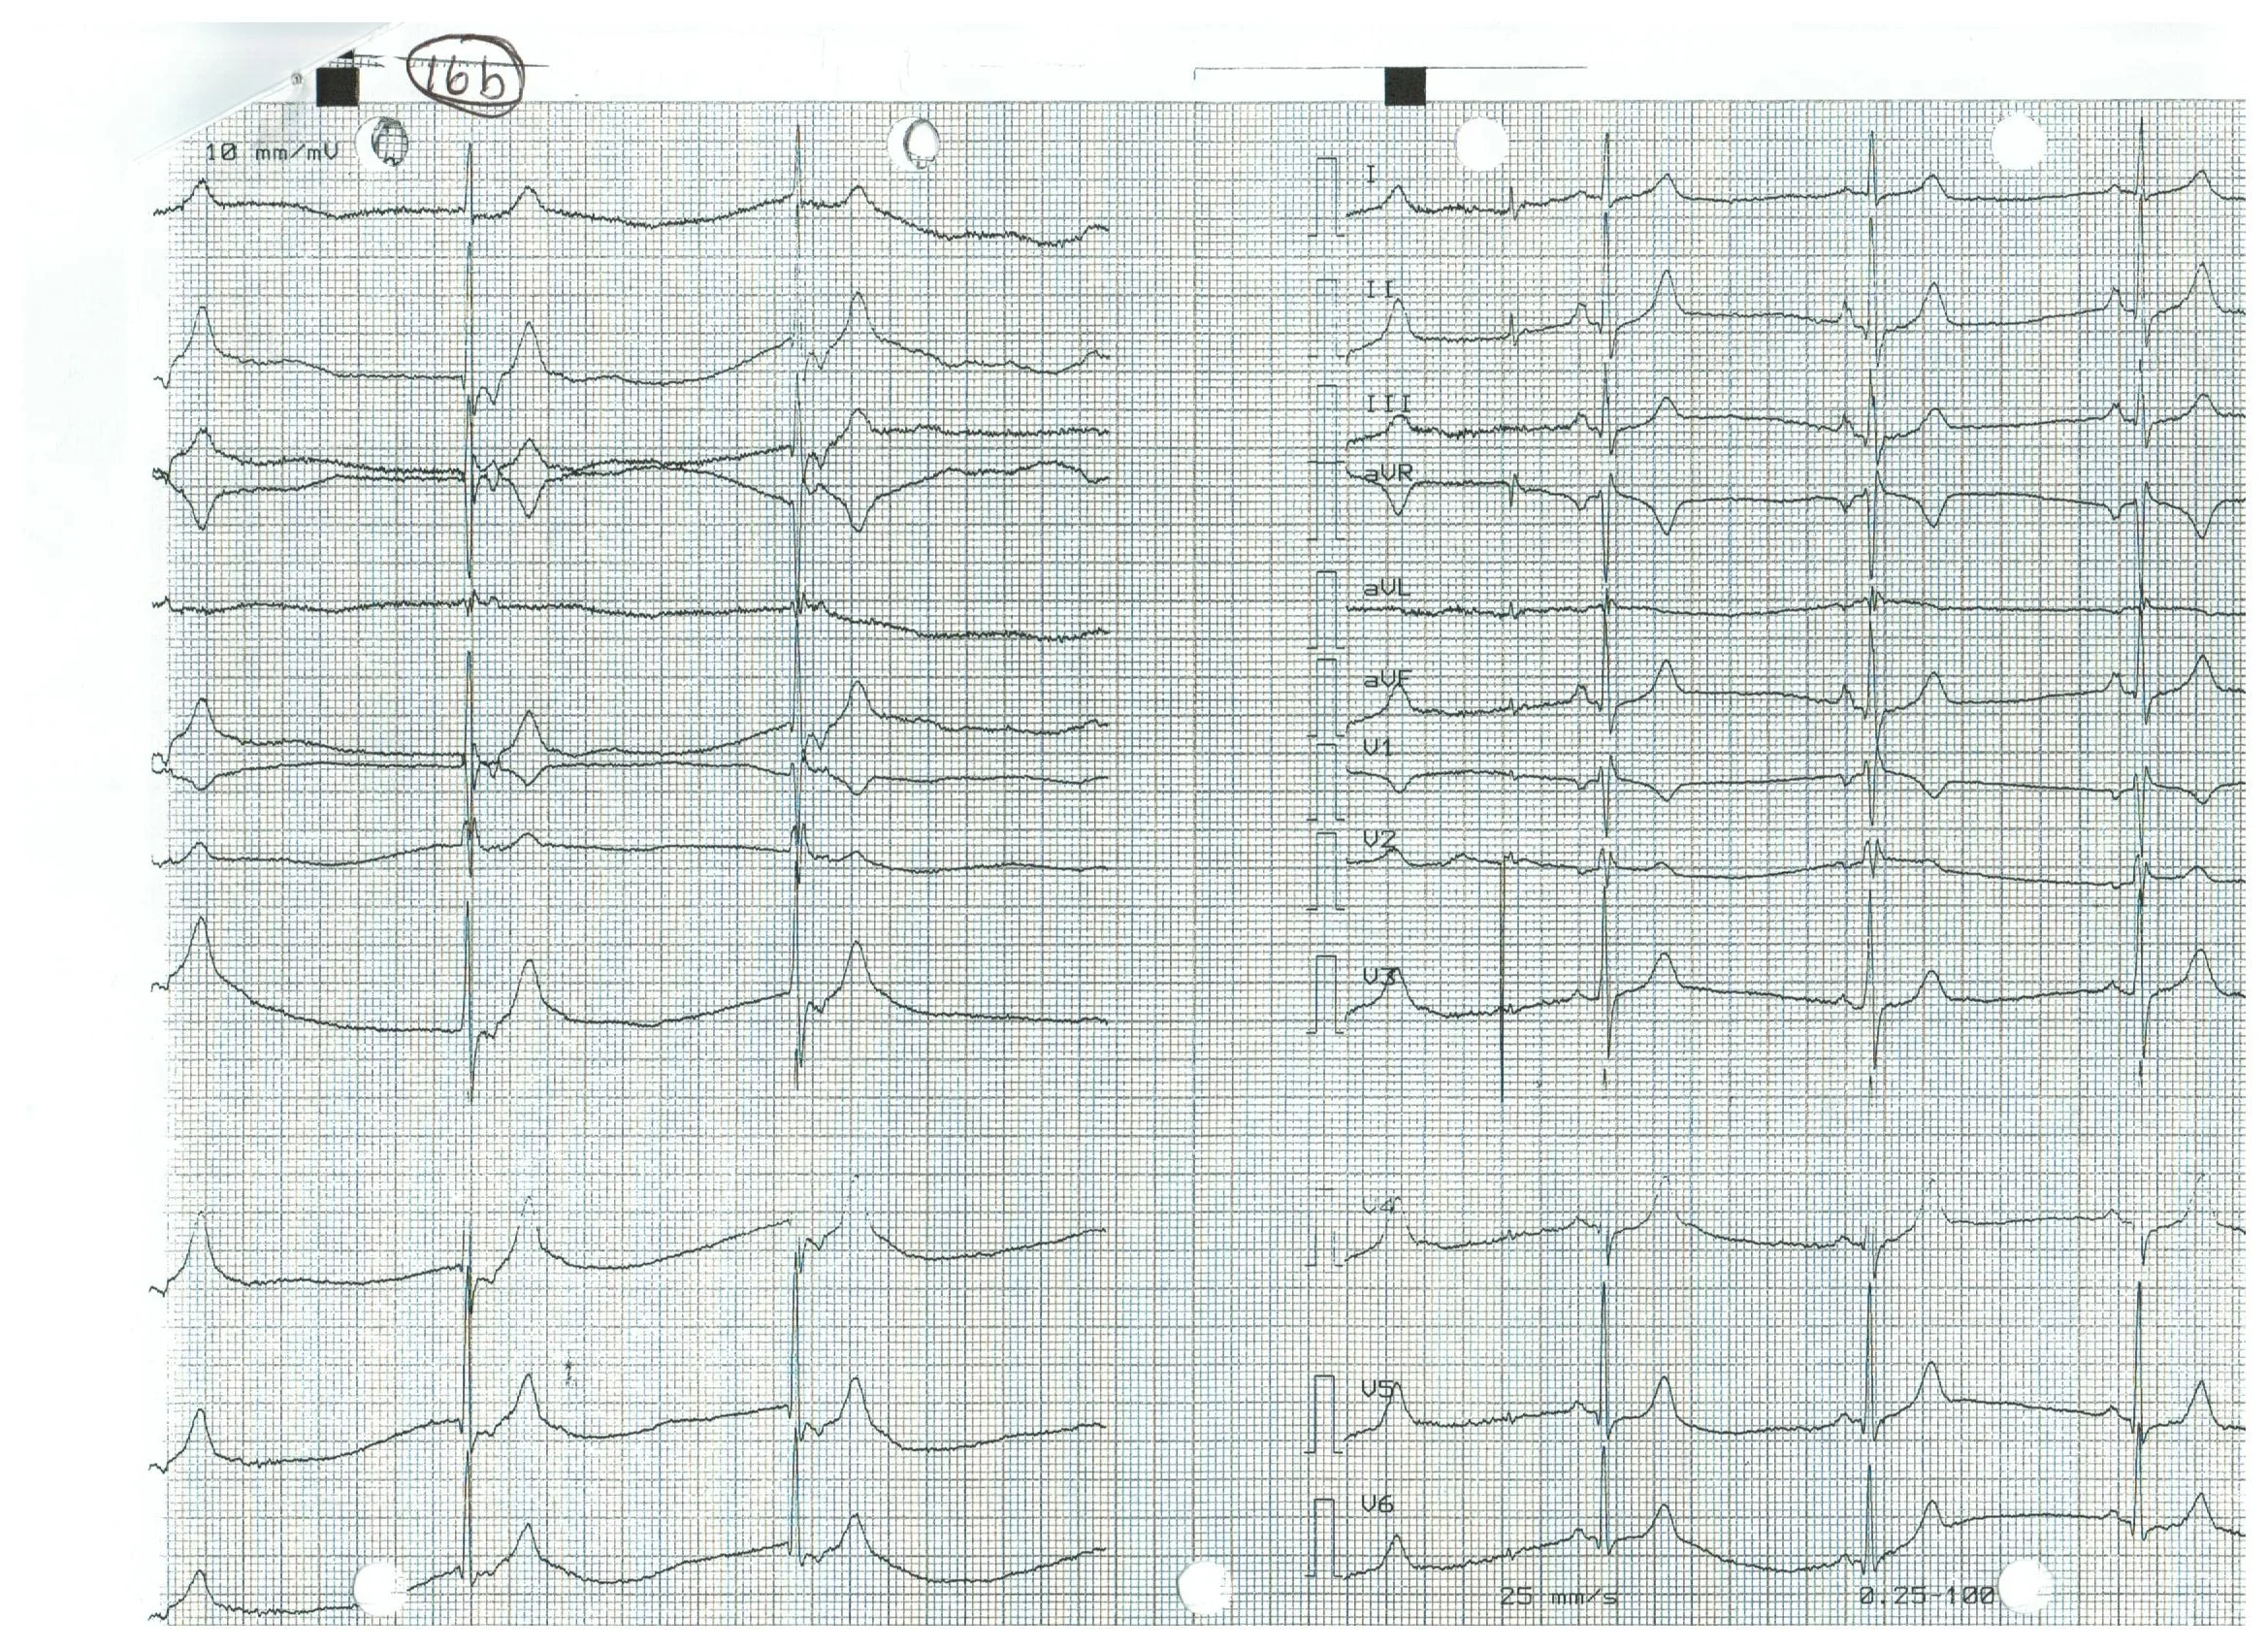

EKG 16b.jpeg